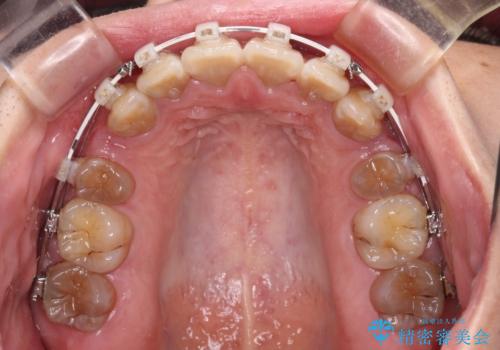

- 審美装置

- 口元の突出感を気にして来院された患者様です。

上下前歯が著しく前突している状態であったので、上下左右の第1小臼歯4本を抜歯し、ワイヤー装置にて矯正治療を行うこととしました。

舌の突出癖により、前突になったと考えられたため、舌のトレーニングをしっかりと行うよう指導しました。